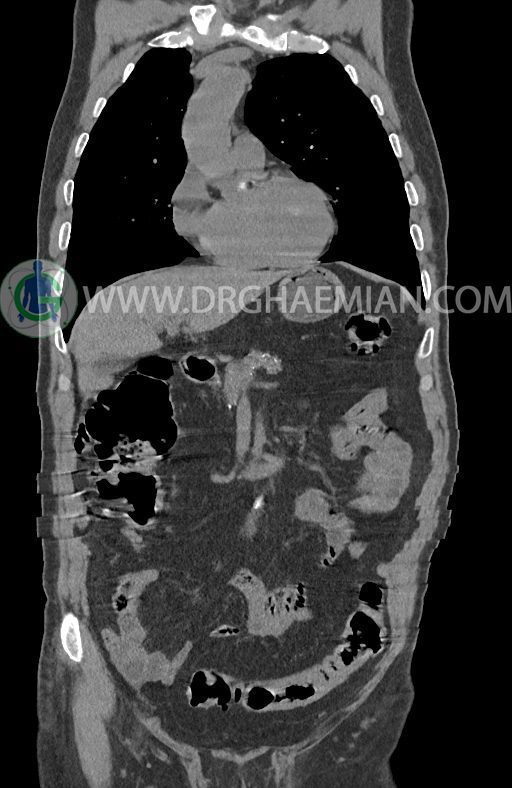

در سی تی اسکن اسپیرال ریه ها و مدیاستن، شکم و لگن با و بدون کنتراست وریدی (مولتی دیدکتور 16 با مقاطع ظریف و بازسازی کرونال) :

–افزایش ضخامت تومورال دیستال مری و GEJ در سگمانی به طول 4cm-5cm (T2 or T3)

-3 لنف نود رژیونال با SAD ≤ 9 mm دیده می شود. (N2)

–آتروفی نسبی پانکراس همراه با فوکوس های کلسیفیه ی منتشر پارانشیم مطرح کننده ی پانکراتیت مزمن

نتیجه : T(2or3)/N2/M0